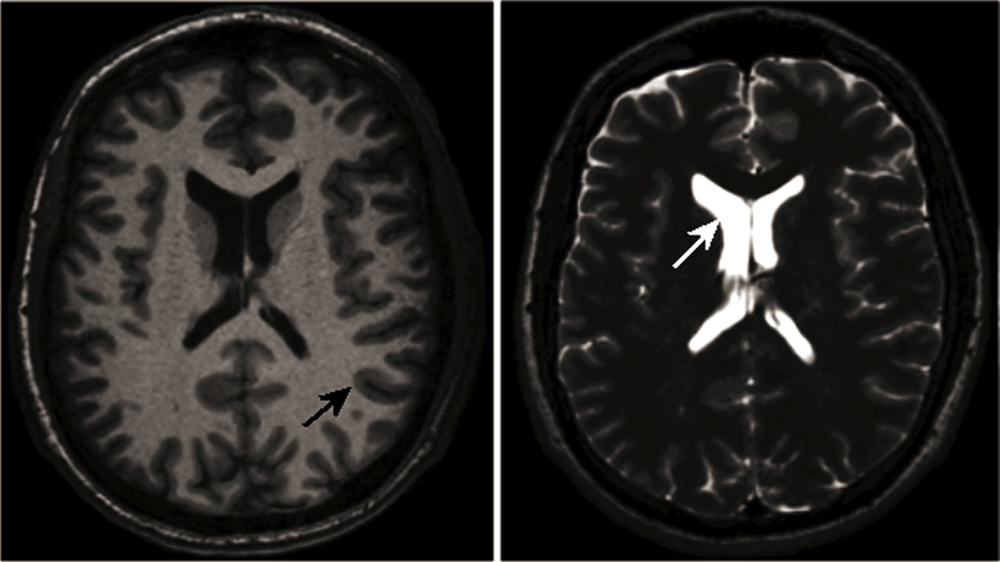

2.1. High-Resolution Structural MRI

- Theysohn, J.M.; Kraff, O.; Maderwald, S.; Schlamann, M.U.; de Greiff, A.; Forsting, M.; Ladd, S.C.; Ladd, M.E.; Gizewski, E.R. The human hippocampus at 7 T—in vivo MRI. Hippocampus 2009, 19, 1–7. [Google Scholar]

- Nakada, T.; Matsuzawa, H.; Igarashi, H.; Fujii, Y.; Kwee, I.L. In vivo visualization of senile-plaque-like pathology in Alzheimer’s disease patients by MR microscopy on a 7T system. J Neuroimaging 2008, 18, 125–129. [Google Scholar]